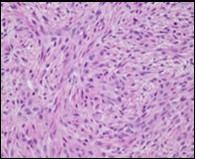

Figure 1.Low grade fibromyxoid sarcoma enunciating fibrous and myxoid zones of uniform spindle-shaped tumour cells with absence of atypia 9.

Macroscopically,the neoplasm is gradually progressive, painless, firm, tan coloured, well circumscribed, grossly infiltrative, soft tissue mass of magnitude varying from one centimetre to 18 centimetres, commonly of 6 centimetres diameter. Cut surface is fibrotic with focal myxoid areas4. On fine needle aspiration cytology, the cellular neoplasm is configured by spindle-shaped cells. Tumour cells contain scant, wispy cytoplasm, uniform, elongated nuclei and miniature, inconspicuous nucleoli. The background is prominently myxoid. Significant nuclear pleomorphism or mitotic activity is absent. However, cogent diagnosis on cytology may be challenging 4.5. On low power, the well demarcated neoplasm is composed of alternating foci of myxoid and fibrous tissue. Giant rosettes are intermingled with zones of whorled cellular aggregates recapitulating preliminary rosettes.

Bland tumour cells depict monotonous, hyperchromatic nuclei. Tumour areas can exhibit prominent curvilinear, arching or plexiform vasculature. Mitotic activity is exceptional 4, 5.

Typically, low grade fibromyxoid sarcoma is comprised of a whorled cellular pattern with intermingled fibrous and myxoid areas. Also, minimally cellular areas of collagenous tissue are denominated, composed of uniform spindle-shaped cells4, 5. Unique morphologic pattern of hyalinising spindle cell tumour configuring giant rosettes can appear in certain low grade fibromyxoid sarcomas4, 5.

The minimally to moderately cellular neoplasm is composed of bland, fusiform or spindle-shaped cells with scarce cytoplasm and angulated nuclei. Also, whorled cellular aggregates are exhibited. Focal to diffuse cellular whorls are intermingled within a dense, collagen-rich stroma. Abrupt, focal transition to myxoid areas can be discerned. Roughly 45% neoplasms depict foci of epithelioid cells. Nearly 40% tumours display enlarged, inadequately configured collagen rosettes2, 4.

The neoplasm frequently infiltrates abutting skeletal muscle. Occasionally, tumefaction denominates hyper-cellular foci, tumour necrosis, cellular or nuclear atypia and mitotic figures, features which are characteristic of intermediate to high grade sarcoma. Localized tumour reoccurrence may be hyper-cellular with enhanced mitotic activity 4, 5. On ultrastructural examination, fibroblastic differentiation is exemplified 5. Figure 1, Figure 2, Figure 3, Figure 4, Figure 5, Figure 6, Figure 7, Figure 8.